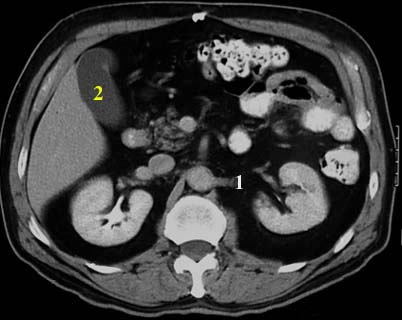

Abdominal aorta

Inferior vena cava

Portal vein

Splenic vein

Superior mesenteric artery

Superior mesenteric vein